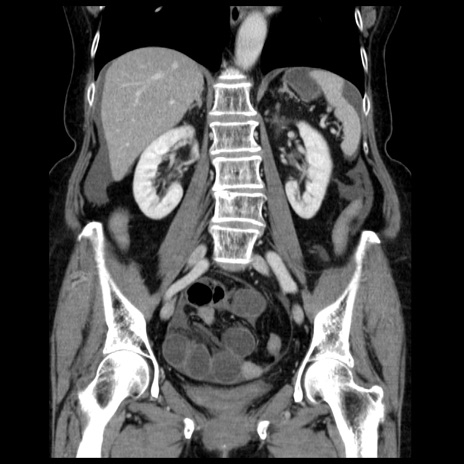

症例13(冠状断像)

【症例】70歳代女性

【主訴】腹痛、嘔吐

【現病歴】15時間程前(昨晩)より腹痛あり。今朝になっても症状の改善なく、嘔吐あり。腹痛も増悪あり、救急外来受診。

【既往歴】子宮癌全摘術後

【身体所見】意識清明、BP 121/72mmHg、P 74bpm、SpO2 100%(RA)、腹部:平坦・軟、腸雑音ほぼ聴取せず。下腹部・心窩部・臍左上に圧痛あり。反跳痛なし。

【データ】WBC 10600、CRP 0.15